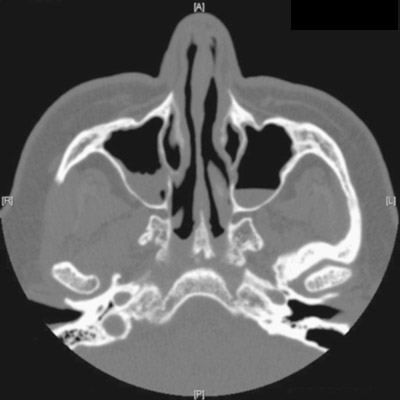

The FP reviewed the CT scan and noted that the patient had air-fluid levels in both maxillary sinuses and loculated fluid on the right side. The patient was given a diagnosis of bilateral maxillary sinusitis that was not responding to the original antibiotic.